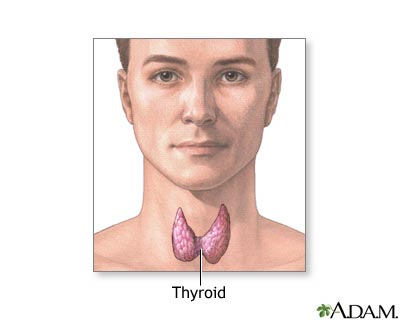

Papillary carcinoma of the thyroid is the most common cancer of the thyroid gland. The thyroid gland is located in front of the lower neck.